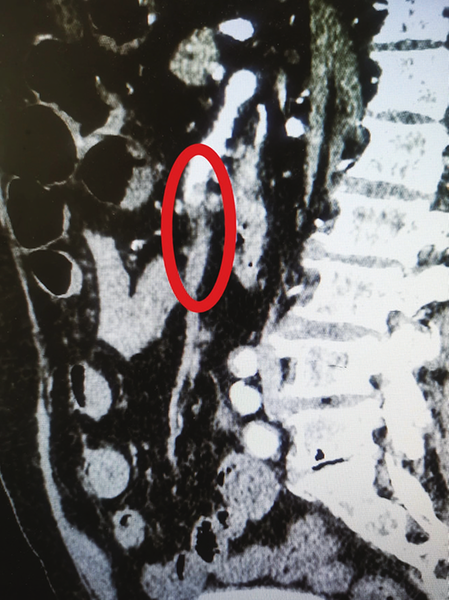

腹部增强CT:图中标识处以远造影剂未显影提示血管栓塞